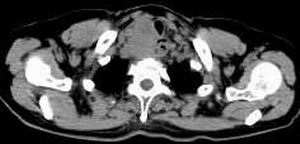

女,61岁,吞咽困难(包括开水)已久。

食道中上段癌并锁骨上窝淋巴结转移.

1、同意食道上段ca併淋巴结转移。

2、做食道呑钡就一目了然。

3、右侧甲状腺是否有问题?是否甲状腺ca转移食道上段。因为肿块顶部图像没有,请楼主展示,谢谢!

食道中上段中分化鳞癌伴锁骨上淋巴结转移

大家都很正确,谢谢!